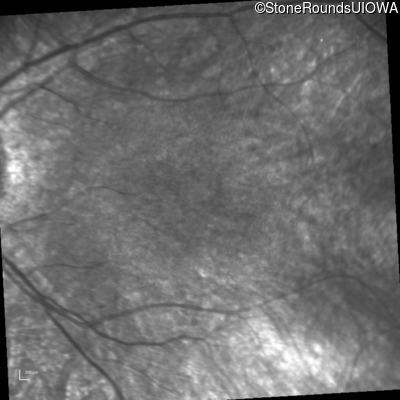

Infrared Fundus Photograph - Right - 20/80 -1

Exemplar